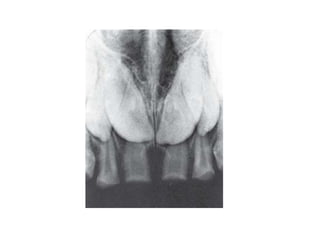

• Mesiodens

6. Fusion

Merupakan hasil dari penggabungan dua

benih gigi bersebelahan yang sedang

berkembang.

8. Gemination

Merupakan anomali yang terjadi ketika satu

tooth bud berusaha untuk membelah.